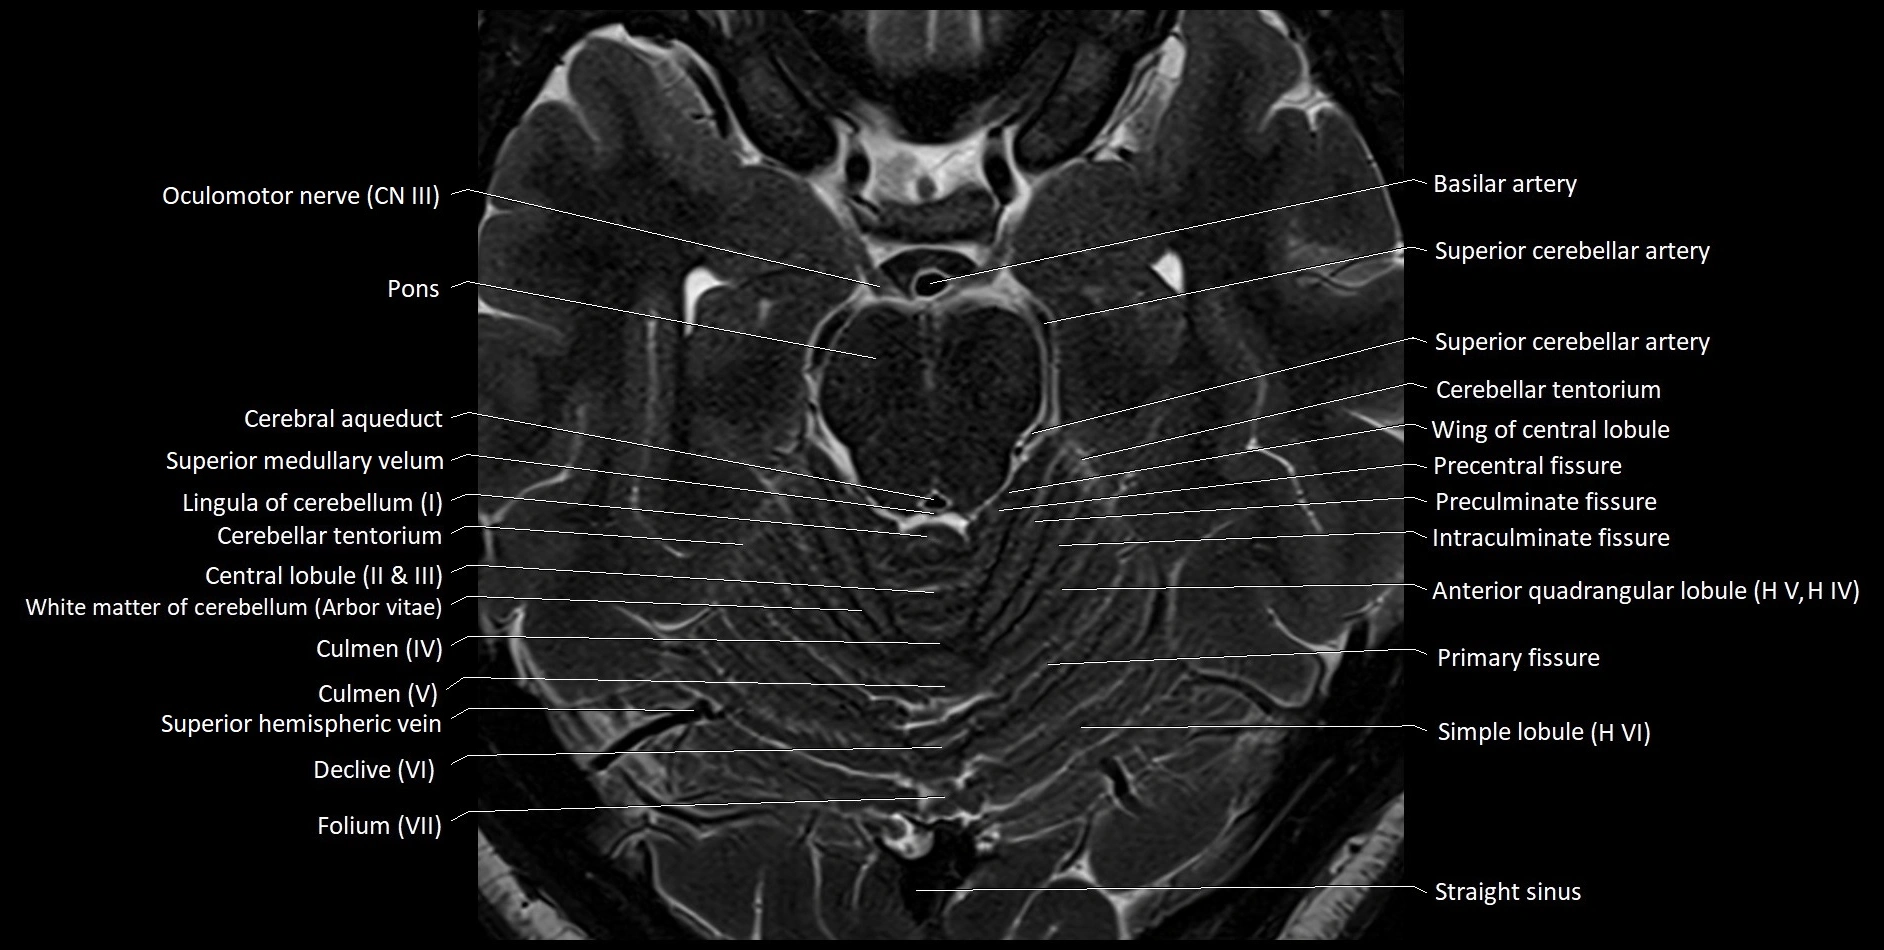

MRI images